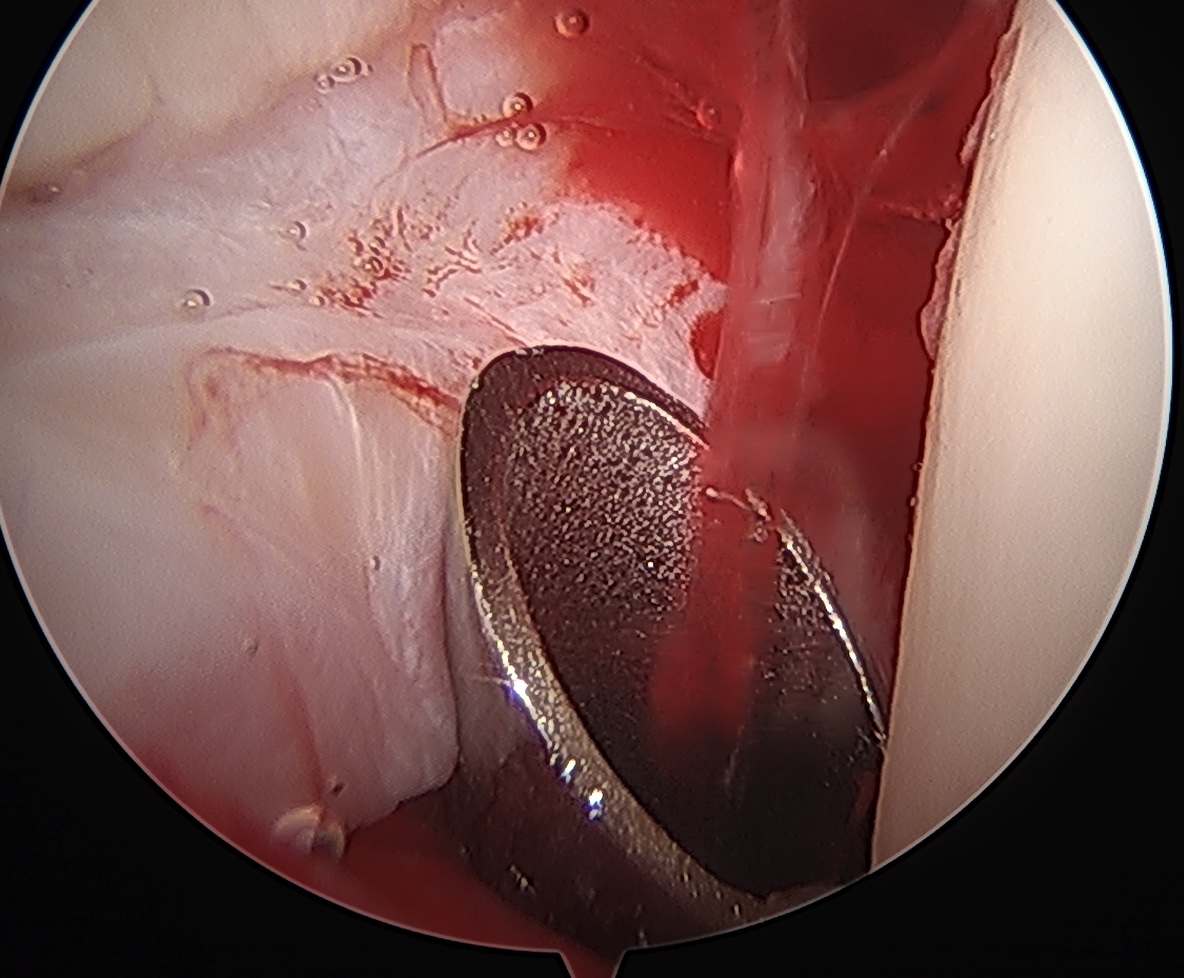

Acetabular rim trim / Acetabuloplasty

Pincer resection

Os acetabuli resection

Labral repair

CAM resection